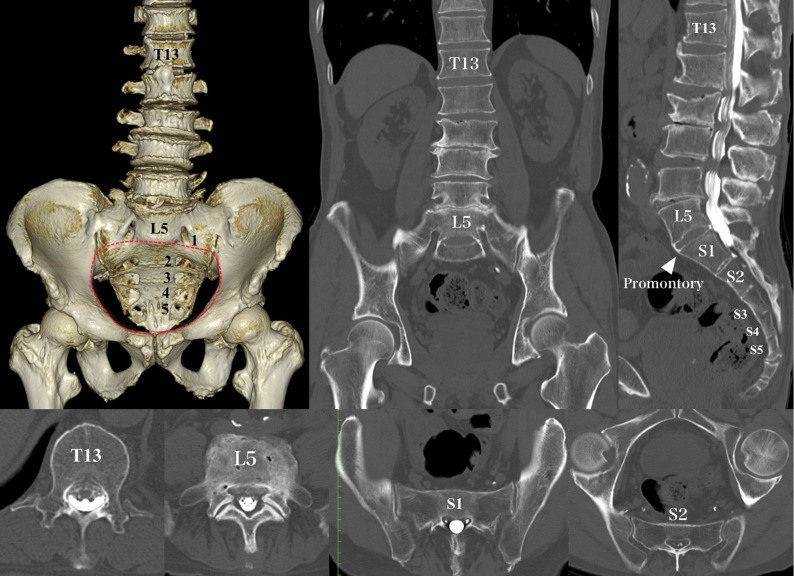

A normal sacrum has 5 sacral vertebrae and 4 sacral foramina. Type-IIIb LSTV (Fig. 2) appeared to have 6 sacral vertebrae on sagittal CT images and 5 sacral foramina on 3-dimensional CT images. Closer scrutiny of the position of the promontory on the arcuate line of the ilium on 3-dimensional CT images revealed that type-IIIb LSTV was positioned above the arcuate line and was identified as the lowest lumbar vertebra. We identified a different LSTV type than type-IIIb LSTV and named it “S6 LSTV” (Fig. 3). Patients with S6 LSTV had 6 sacral vertebrae and 5 sacral foramina below the arcuate line of the ilium. However, demonstrating the difference between type-IIIb LSTV and S6 LSTV based on radiographs only was difficult (Fig. 4).

Fig. 3.

CT images demonstrating an S6 LSTV case. The 3-dimensional CT image and sagittal CT image show 6 sacral vertebrae and 5 sacral foramina below the promontory, indicating S6 LSTV and it is positioned below the arcuate line (red dotted line). In this case, the combination of presacral vertebrae is T13 and L4, and bilateral dysplastic ribs of T13 are type B (hypoplastic). The S1 upper segment has an L5-like morphology as the upper segment seems to have the equivalent of a transverse process and does not articulate with the ilium, whereas the S2 level appears normal.